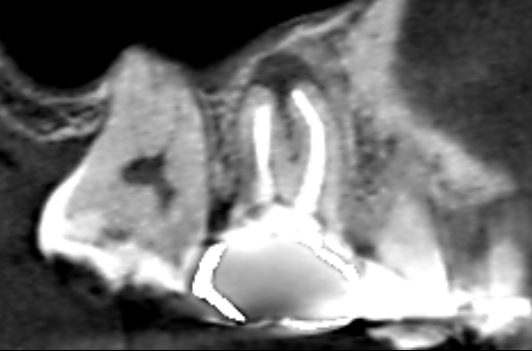

続きを読むVol.20 上顎洞内の炎症が根管治療で改善したケース

- 上顎洞炎と歯の関係・ 副鼻腔炎が治らない時は歯が原因かも・ 抜歯を避ける治療・ 歯の膿と鼻の病気・ 精密根管治療

他医院で詰め物をした歯が痛くなったということで当医院にいらした患者さんです。上顎第一大臼歯の詰め…